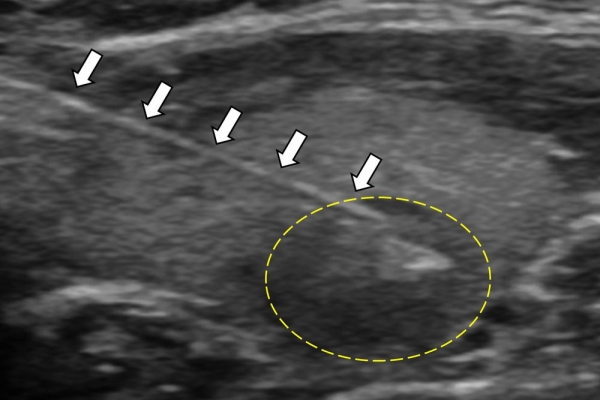

Η διαδερμική βιοψία είναι μία ελάχιστα επεμβατική μέθοδος λήψης υλικού από τον όγκο για κυτταρολογική και ιστολογική εξέταση, από εστιακές αλλοιώσεις του ήπατος, πνεύμονα, νεφρού κλπ. Συστήνεται από τον κλινικό ιατρό ανάλογα με το είδος και το μέγεθος της βλάβης και πραγματοποιείται με ασφάλεια από επεμβατικό ακτινολόγο με την καθοδήγηση αξονικού τομογράφου ή υπερήχων. Στη σύγχρονη ογκολογική θεραπεία όπου γίνεται προσπάθεια καταπολέμησης του καρκίνου σε μοριακό επίπεδο κρίνεται αναγκαία η ακριβής ιστολογική ταυτοποίηση του όγκου ώστε να εφαρμοσθεί εξατομικευμένη θεραπεία για το βέλτιστο αποτέλεσμα. Οι κατευθυνόμενες βιοψίες στοχευουν στο να παρέχουν στον κλινικό ογκολόγο το απαραίτο ιστοπαθολογικό υλικό που θα του επιτρέψει να εφαρμόσει την κατάλληλη θεραπεία για τον ογκολογικό ασθενή.